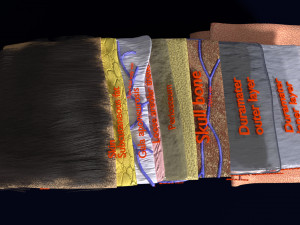

A blend model of brain along with its covering layers (meninges), skull bone and scalp labelled in detail and anatomically precise. The parts depicted are white, gray, pia, arachnoid, dura, bone, skin, fat, aponeurosis, periosteum, falx cerebri and more.

The material is high resolution image textures and normal maps based on non overlapping UVs. The texture and normal maps are packed with the blend file itself.